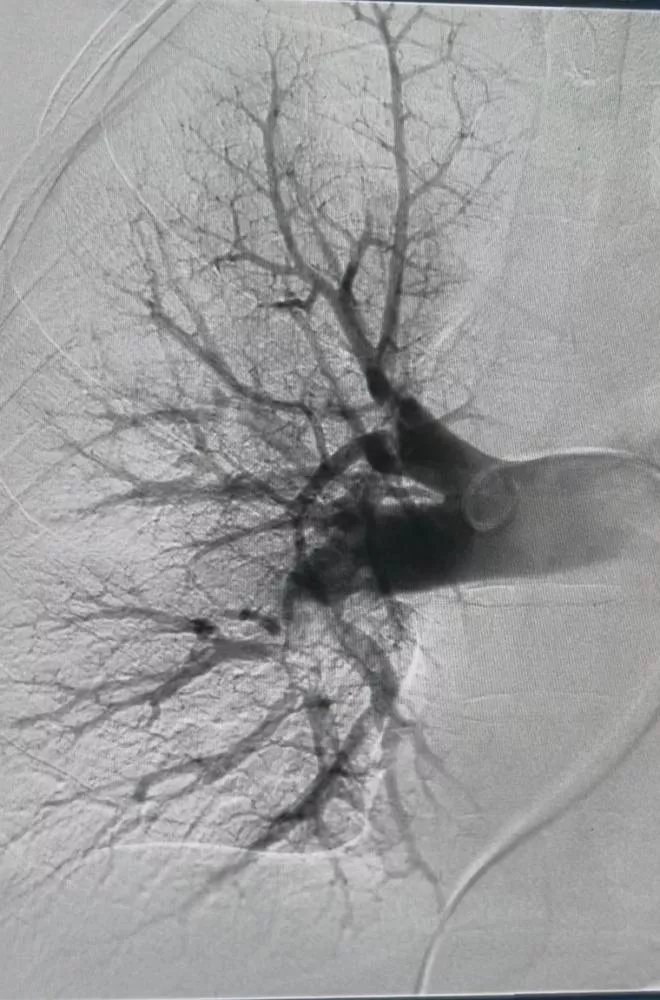

Isaac deu entrada na unidade com queixa de dor respiratória e, após avaliação clínica e exames de imagem, foi confirmada a presença de um coágulo de grandes proporções obstruindo a circulação nos vasos do pulmão. A obstrução comprometia o fluxo sanguíneo adequado, o que levou à indicação imediata da trombectomia mecânica pulmonar.

Segundo o cardiologista intervencionista Jean Santiago, a trombectomia mecânica pulmonar consiste na retirada do coágulo de sangue diretamente da artéria pulmonar, permitindo o restabelecimento do fluxo sanguíneo normal. O procedimento foi realizado em caráter de urgência e teve êxito, possibilitando a rápida estabilização do quadro clínico do paciente, que segue em programação de alta hospitalar.

Mesmo não estando de plantão no momento, Jean se deslocou até a unidade para realizar o procedimento. Segundo ele, a decisão foi imediata diante da gravidade do caso. “Era um paciente jovem, em estado grave. Se o procedimento não fosse realizado, ele não sobreviveria. A trombectomia mecânica era a única chance. Graças à estrutura que temos hoje e ao material disponível, conseguimos realizar o procedimento com sucesso. Hoje, o paciente está vivo e prestes a receber alta”, destacou o médico.